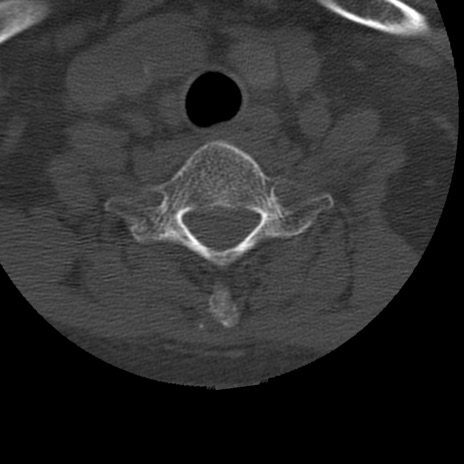

症例50 頚椎CT(横断像)

頚椎CT